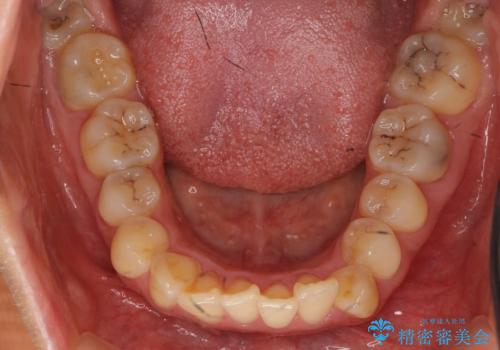

- 前歯の突出を主訴に来院。

上の奥歯を後ろに下げて治療をしました。

上の前歯もIPR(エナメル質をわずかに削る処置)を行っています。